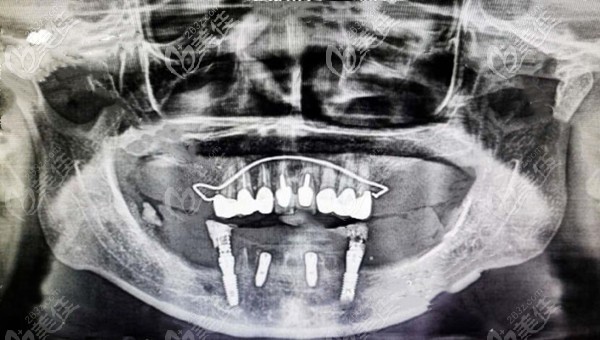

患者牙齒情況:男,60歲,因牙周病導致下頜大部分缺損,長達十余年,咀嚼困難。

治療計劃:allon4半口種植牙修復,馬龍橋+氧化鋯全瓷

60多歲老人牙齒缺失情況圖▼

下頜半口馬龍橋修復效果圖▼